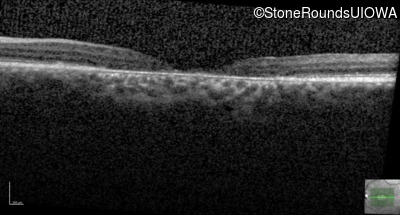

Age at visit: 29 years

This 29-year-old man had good vision until his early 20's. at which time he began to experience a slow reduction in his acuity. His driver's license was restricted at age 27.

Age at visit: 29 years (Visit 2)